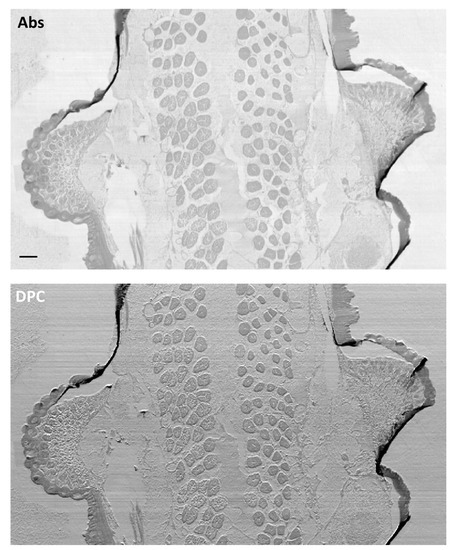

- Pascolo, L.; Sena, G.; Gianoncelli, A.; Cernogoraz, A.; Kourousias, G.; Metscher, B.D.; Romano, F.; Zito, G.; Pacilè, S.; Barroso, R.; et al. Hard and Soft X-ray Imaging to Resolve Human Ovarian Cortical Structures. J. Synchrotron Radiat. 2019, 26, 1322–1329. [Google Scholar] [CrossRef] [PubMed]

- Pascolo, L.; Venturin, I.; Gianoncelli, A.; Salomé, M.; Altissimo, M.; Bedolla, D.E.; Giolo, E.; Martinelli, M.; Luppi, S.; Romano, F.; et al. Morphological and Chemical Information in Fresh and Vitrified Ovarian Tissues Revealed by X-ray Microscopy and Fluorescence: Observational Study. J. Inst. 2018, 13, C06003. [Google Scholar] [CrossRef]

- Pascolo, L.; Venturin, I.; Gianoncelli, A.; Bortul, R.; Zito, G.; Giolo, E.; Salomé, M.; Bedolla, D.E.; Altissimo, M.; Zweyer, M.; et al. Light Element Distribution in Fresh and Frozen–Thawed Human Ovarian Tissues: A Preliminary Study. Reprod. Biomed. Online 2018, 37, 153–162. [Google Scholar] [CrossRef]